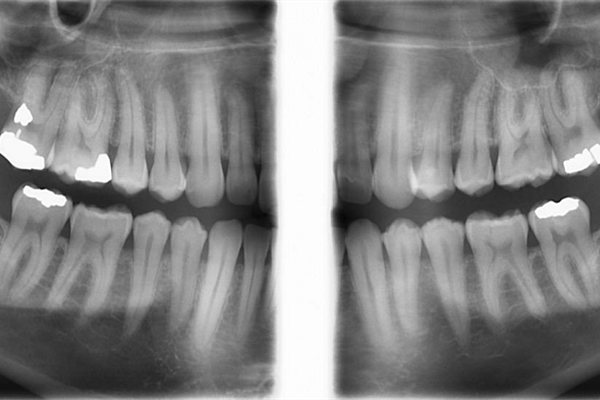

در این تکنیک رادیوگرافی بایت وینگ بدون قرار دادن گیرنده یا وسیله دیگری در داخل دهان، تهیه میشود. کودکان اغلب از جایگزاری گیرنده های رادیوگرافی در داخل دهان امتناع میورزند و تصویرداریهای داخل دهانی برای کودکان اغلب امری ناخوشایند است. بدین منظور، تهیه رادیوگرافی بایت وینگ که از کلیشه های مهم تصویربرداری کودکان میباشد، در این مرکز صورت خارج دهانی قابل انجام است. این تکنیک همچنین میتواند جایگزین مناسبی برای بایت وینگ داخل دهانی در افراد بزرگسالی باشد که به دلیل تهوع شدید، امکان تحمل گیرنده را در داخل دهان خود ندارند. لازم به ذکر است بالاترین رزولوشن و وضوح تصویر در رادیوگرافی های داخل دهانی مشاهده می شود.